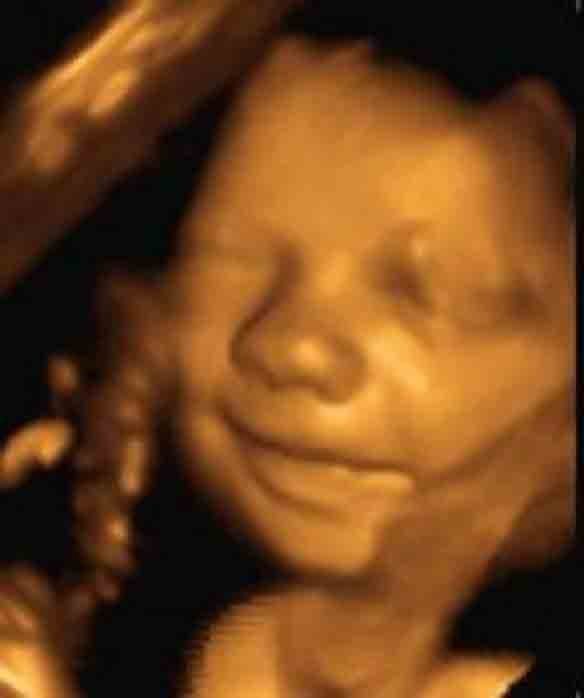

Em bé với nụ cười tươi rạng rỡ và gương mặt dễ thương khi nằm trong bụng mẹ.